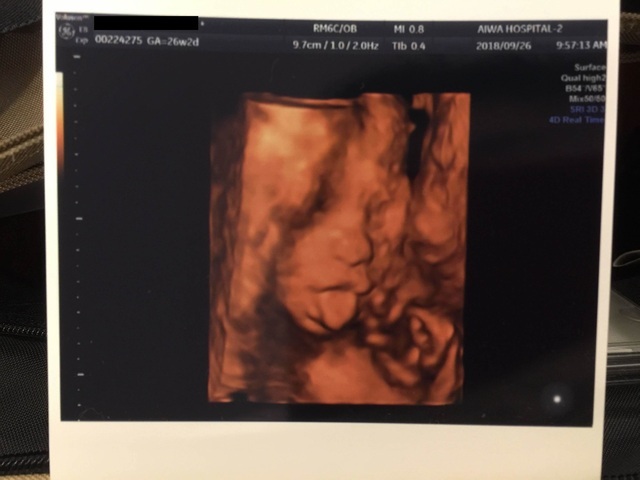

26週2日(26w2d・女の子)|ゆゆあ さん(26歳)

エコー写真撮影時のエピソード:

里帰りして病院がかわりドキドキの中、前の病院ではなかった4Dエコー。お顔は見せてくれなかったけれど、立体的な我が子に感動しとてもうれしかったのを覚えています。

生まれてきて会えるのがさらに楽しみになりました。